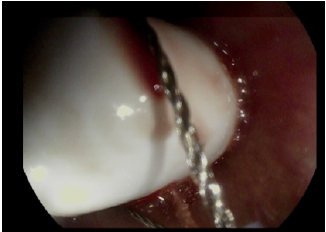

A 68-year-old man affected by liver cirrhosis was admitted for capsule endoscopy because of severe anemia due to overt gastrointestinal bleeding. A capsule enteroscopy was already performed two years earlier for the same reason and the procedure had no complications, showing the presence of petechiaes in the small bowel as sign of portal hypertension. After starting beta blockers therapy the patient had no more episodes of anaemia for the subsequent 18 months; anyway, blood transfusions have been necessary because of overt bleeding in the last 6 months. For this reason, he was referred to our Centre for capsule enteroscopy after a colonoscopy and an upper endoscopy reported no bleeding signs. Actually, the upper endoscopy revealed the presence of a Zencker diverticulum; moreover, an Rx of the esophagus confirmed its presence; nevertheless, the patients did not mention it and didn’t show any records to the physician during the interview before the procedure. The patient swallowed the capsule (Pillcam SB3, Medtronic) smoothly without real-time monitoring. The capsule recording was examinated on the following day, and showed persistent esophageal mucosa images, so it was suspected to be stuck in a Zenker diverticulum. The patient was asymptomatic, but he was unable to report capsule excretion. A neck radiograph was performed, showing a radiopaque foreign body, compatible with the capsule, retained in the patient’s neck. Due to the risk of a spontaneous expulsion of the capsule in the upper airways, it was decided to remove it. The patient underwent upper endoscopy, and the capsule was extracted after several efforts (Figures 1 & 2). On the subsequent days, the patient had an uneventful course and was discharged in stable clinical conditions.